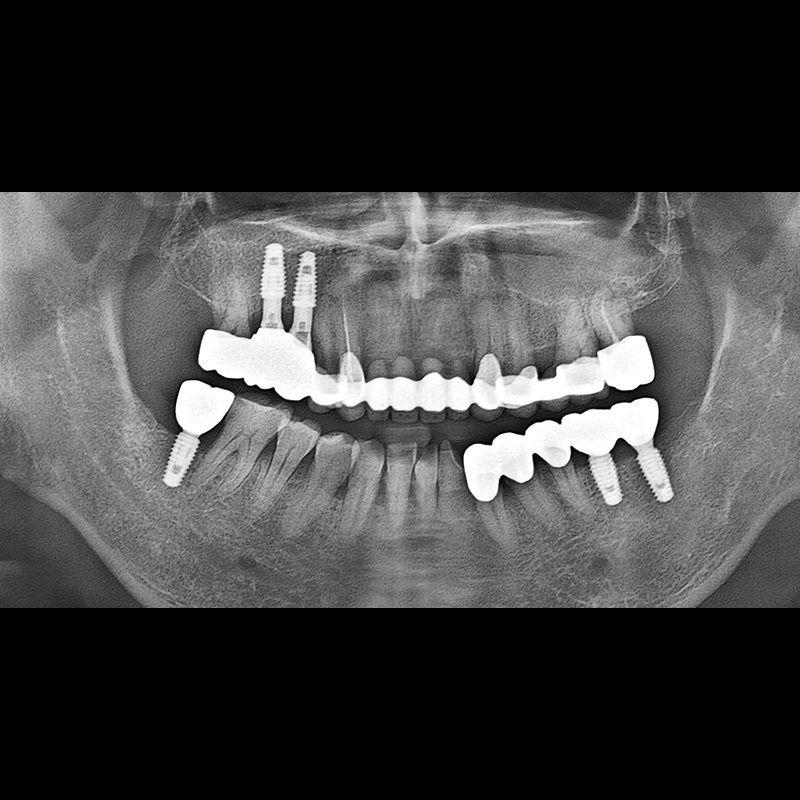

IMPLANT

BEFORE AFTER

种植牙前后的照片 2025.05.30

在缺失的牙齿部分和难以挽救的牙齿位置植入了种植牙。